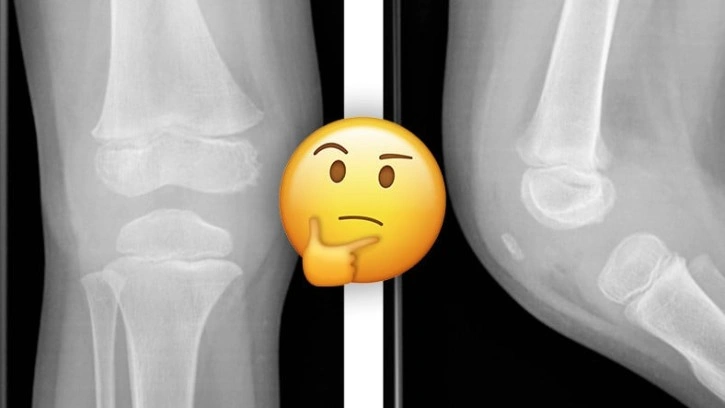

Bu nedenle bebeklerde aslında diz kapağı yok diyemeyiz. Diz kapakları var fakat gelişmeyi bekleyen bir kıkırdak yapıdalar. Hatta öyle ki kıkırdak yapıda oldukları için röntgende görünmezler.

Bir bebek emeklemeye başladığı zaman diz kapağında da gelişme başlıyor. 10 ve 12 yaşlarına gelindiğinde, diz kapağı tamamen kemiksi bir yapıya dönüşmüş oluyor. Yani kıkırdaktan kemiğe dönüşüm süreci yavaş ilerliyor ve uzun yıllar alıyor.